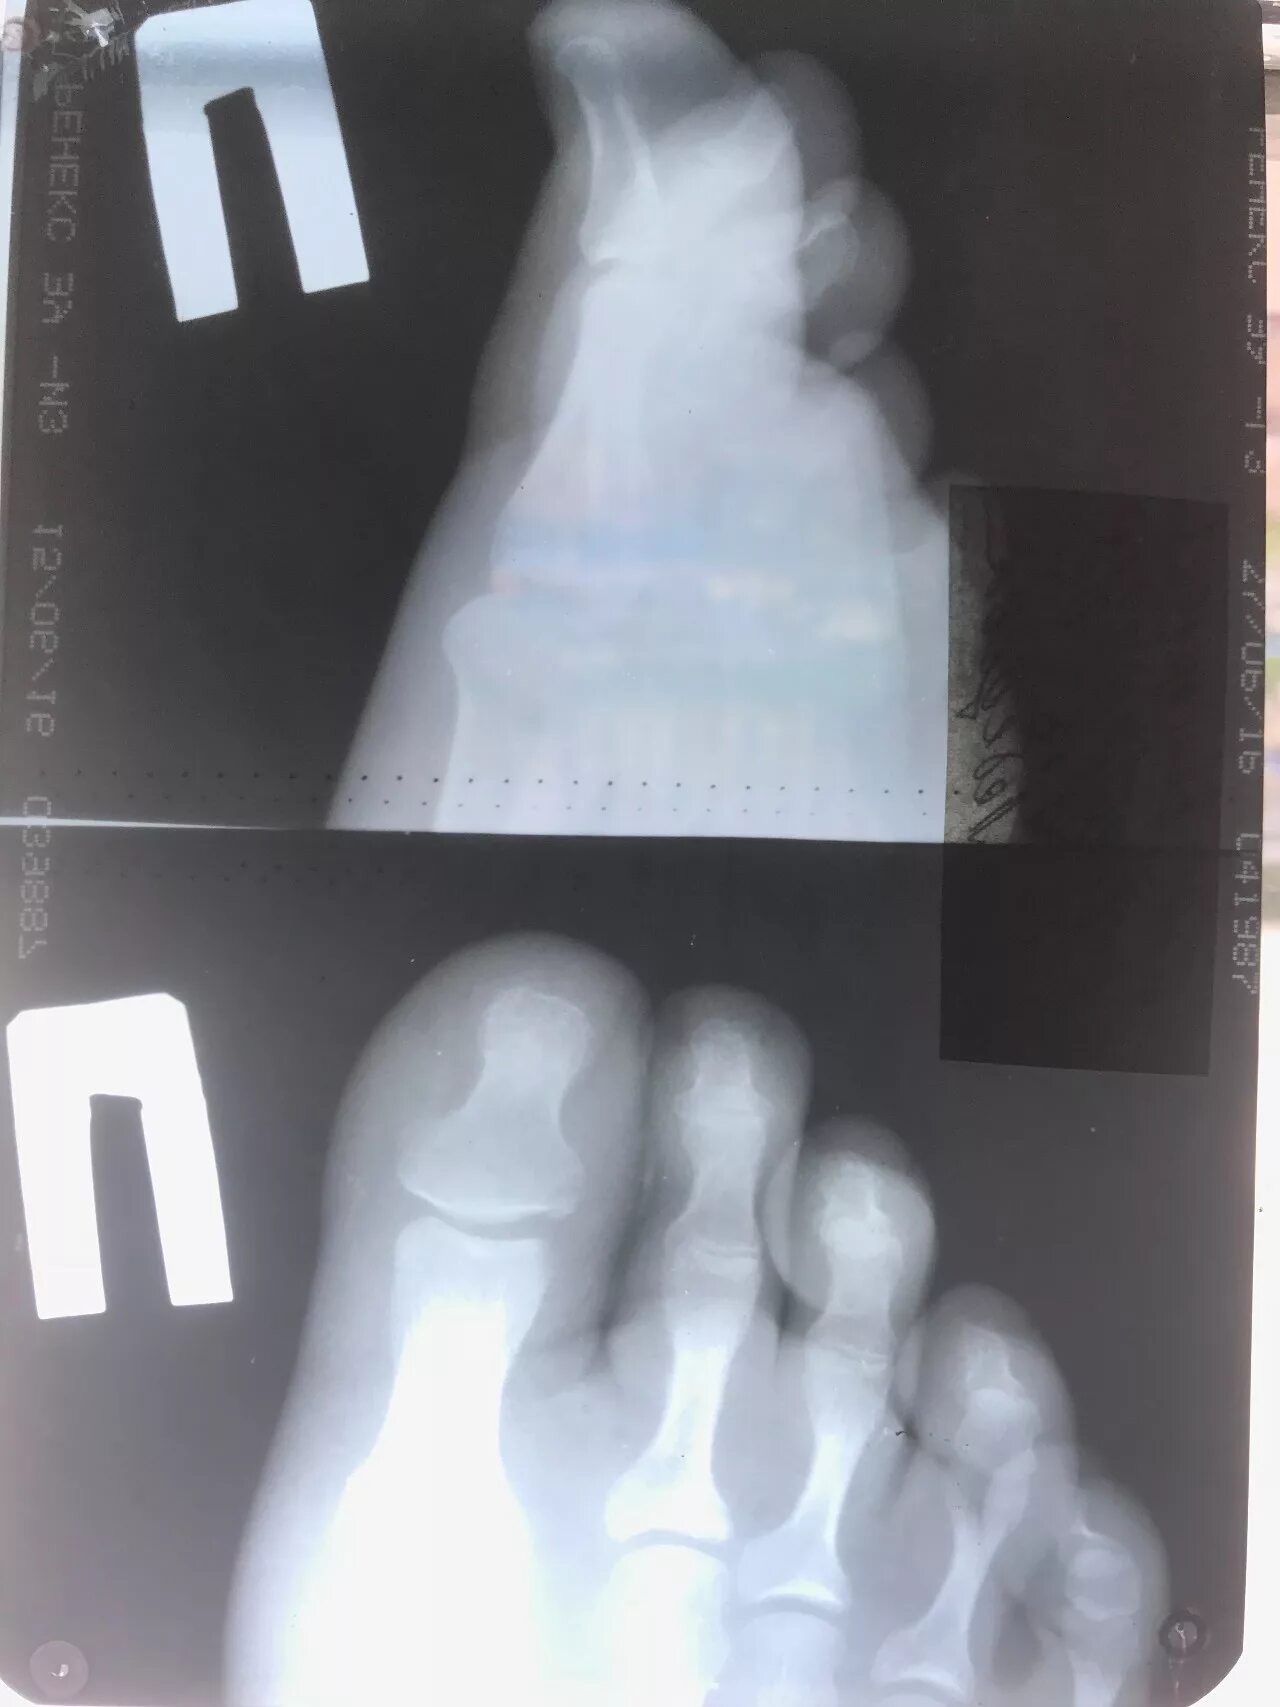

Закрытый перелом пальцев стопы мкб 10